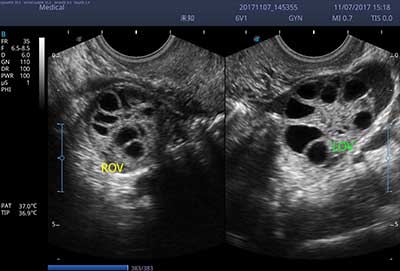

E3便携式彩色多普勒超声诊断系统拥有专业超声技术平台、高度集成化的硬件模块和结构设计、简便的操作流程、支持三探头接口全激活,兼顾了优质图像、轻便机身以及台便两用的临床使用需求。无论在常规超声科门诊检查,还是在急诊、麻醉、ICU、户外等各种应用场景。都能给您带来流程的操作体验。